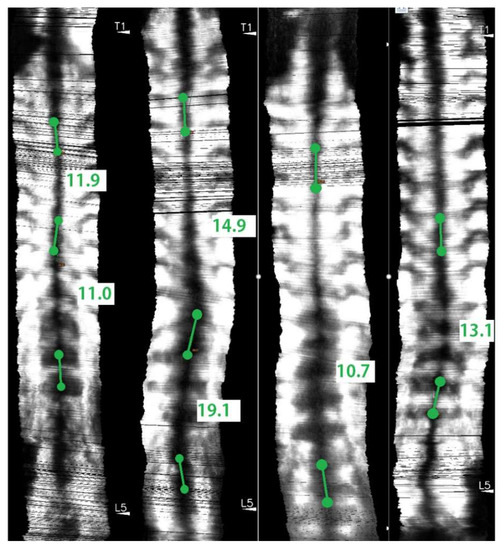

- Cheung, C.W.J.; Zhou, G.Q.; Law, S.Y.; Mak, T.M.; Lai, K.L.; Zheng, Y.P. Ultrasound Volume Projection Imaging for Assessment of Scoliosis. IEEE Trans. Med. Imaging 2015, 34, 1760–1768. [Google Scholar] [CrossRef]

- Zheng, Y.P.; Lee, T.T.Y.; Lai, K.K.L.; Yip, B.H.; Zhou, G.Q.; Jiang, W.W.; Cheung, J.C.W.; Wong, M.S.; Ng, B.K.W.; Cheng, J.C.Y.; et al. A reliability and validity study for Scolioscan: A radiation-free scoliosis assessment system using 3D ultrasound imaging. Scoliosis Spinal Disord. 2016, 11, 13. [Google Scholar] [CrossRef]

- Wong, Y.S.; Lai, K.K.L.; Zheng, Y.P.; Wong, L.L.; Ng, B.K.W.; Hung, A.L.H.; Yip, B.H.K.; Chu, W.C.W.; Ng, A.W.H.; Qiu, Y.; et al. Is Radiation-Free Ultrasound Accurate for Quantitative Assessment of Spinal Deformity in Idiopathic Scoliosis (IS): A Detailed Analysis With EOS Radiography on 952 Patients. Ultrasound Med. Biol. 2019, 45, 2866–2877. [Google Scholar] [CrossRef] [PubMed]

- Lee, T.T.Y.; Jiang, W.W.; Cheng, C.L.K.; Lai, K.K.L.; Castelen, R.M.; To, M.K.T.; Cheung, J.P.Y.; Zheng, Y.P. A novel method to measure the sagittal curvature in spinal deformities: The reliability and feasibility of 3D ultrasound Imaging. Ultrasound Med. Biol. 2019, 45, 2725–2735. [Google Scholar] [CrossRef] [PubMed]